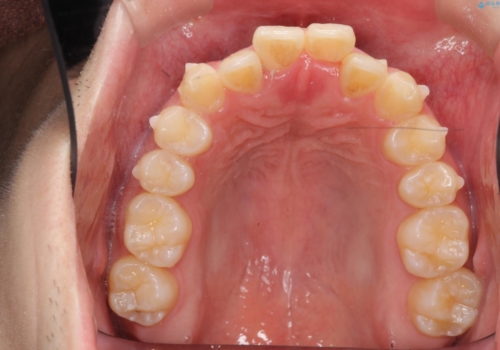

- 前歯のガタガタを主訴に来院。

下の前歯は一本保険治療での被せ物になっており、変色していました。

・神経のない下の前歯を残す

・神経のない歯を抜いてしまって、天然歯で閉じる

のプランを提案し、神経のない前歯を抜く選択をされました。

下の前歯が3本になり奇数になることで、上下の真ん中は一致しませんが、そこまで目立たないと思います。

残りは全て天然歯になり、人工物の心配をしなくて済むようになりました。

上の前歯のガタガタも、わずかに歯を削って並べていますので、出っ歯になったりしないようにしています。